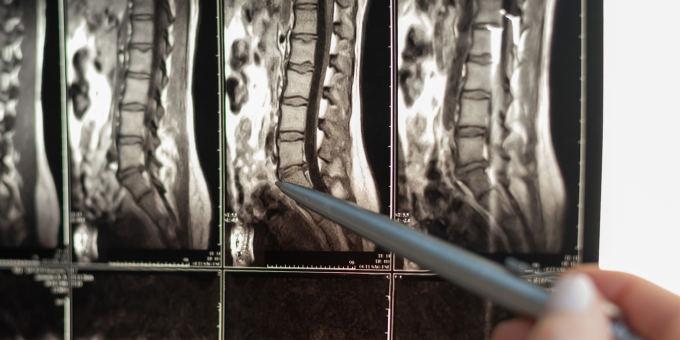

Are you currently in a committed relationship with your couch? Do you spend more time hunched over your laptop than standing upright? If so, you might be unknowingly walking down the increasingly common path of degenerative disc disease (DDD). So, grab a seat fellow desk dwellers – preferably one with lumbar support – while we give you the spine-saving rundown.